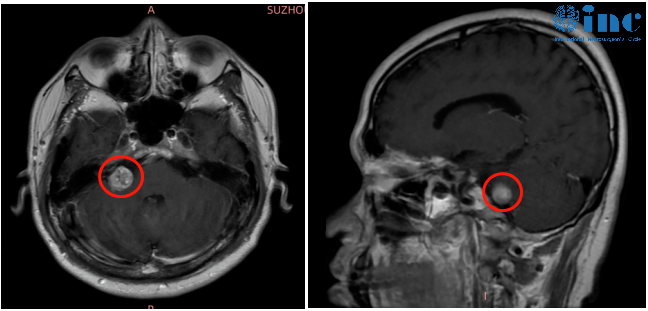

然而進一步的檢查才讓袁先生恐懼,右側(cè)橋小腦角區(qū)結(jié)節(jié),考慮聽神經(jīng)瘤。

腫瘤一大部分長在內(nèi)聽道深處,位置如此刁鉆的腫瘤,手術(shù)難度可想而知。如果想要全切腫瘤不復(fù)發(fā),手術(shù)需要磨除骨質(zhì)極其容易傷及面聽神經(jīng),更容易導(dǎo)致面癱。

“對于內(nèi)聽道型的聽神經(jīng)瘤,自己有相關(guān)成功的經(jīng)驗技術(shù)可以做到順利切除,長期性面癱的風險大概為1-2%。”

內(nèi)聽道磨除術(shù)及修補術(shù)

手術(shù)中巴教授利用其前沿的手術(shù)理念,術(shù)中充分磨開內(nèi)聽道,暴露面神經(jīng)與腫瘤的關(guān)系,是腫瘤全切和大水平保護面神經(jīng)功能的基礎(chǔ)。磨除程度以能全切除內(nèi)聽道內(nèi)腫瘤為宜,不可過度磨除,避免損傷神經(jīng)、頸靜脈球等,否則將會增加手術(shù)風險。

在巴教授前沿手術(shù)理念和高超的手術(shù)技術(shù)下,袁先生的內(nèi)聽道聽神經(jīng)瘤得到順利切除、面聽神經(jīng)得到了功能+解剖保留,無即時面癱、右耳原來所剩的微弱聽力得到保留。